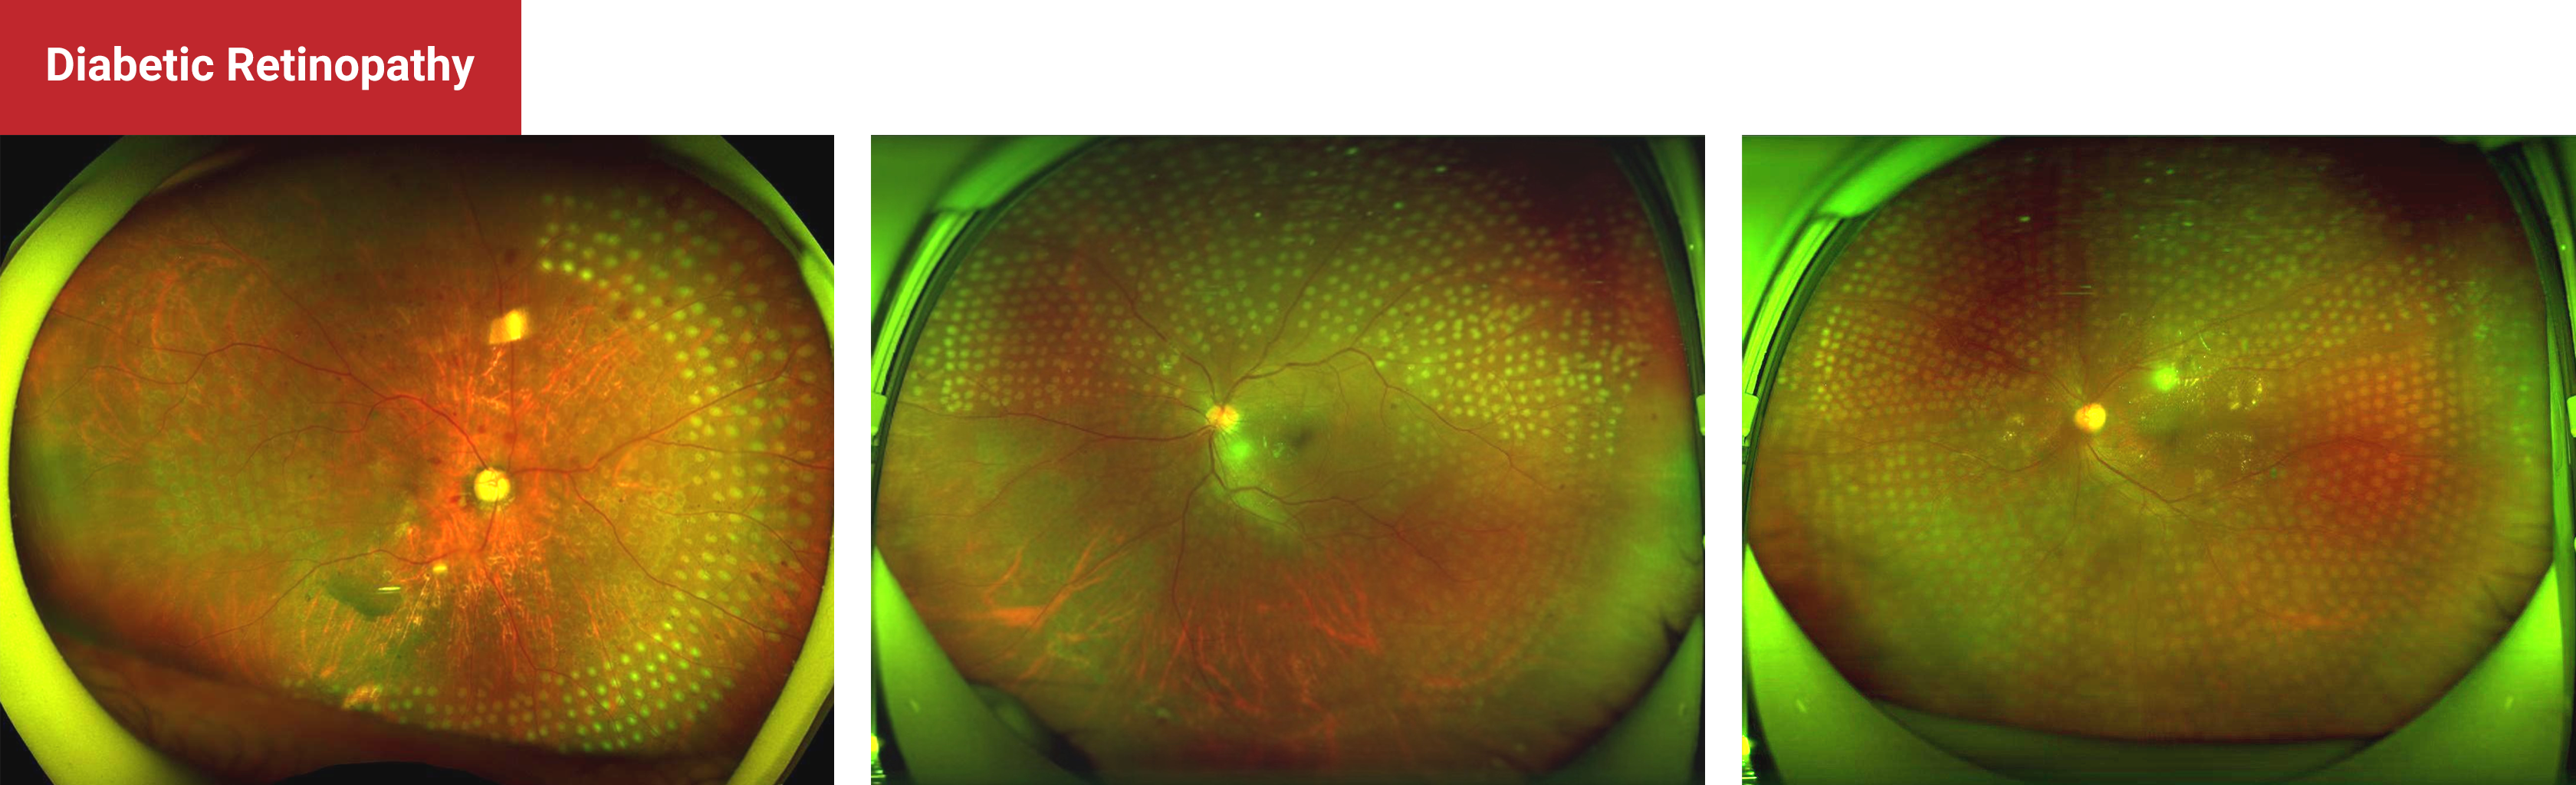

Diabetic Retinopathy

Pan Retinal Photocoagulation